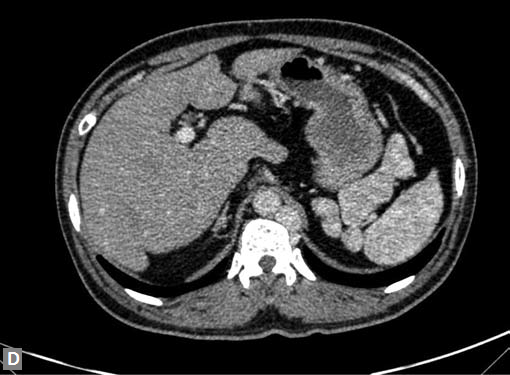

The most common mass lesion in heart is thrombus. Postinfarct clot is common in LV apex. Postinfarct aneurysm of LV may have clot. Rheumatic mitral valve disease with AF has left atrial (LA) appendage thrombus. Large one can extend to body of thrombus. Patients with arrhythmogenic right ventricular dysplasia (ARVD), sarcoidosis can have thrombus in right ventricle. SVC and IVC thrombus can extend to right atrium. Long-standing catheters can be source of thrombus in innominate veins and SVC.

Carcinomas of liver, kidney can directly extend to IVC and then into RA.

Site of the mass and prevailing clinical scenario help to differentiate the clot from neoplasm, although it may not be possible to do the same definitively.

Clots are more likely to have calcific foci (Figs 21I to K) within when they are long standing. Neoplasms with signifi cant neoangiogenesis show discernible contrast enhancement.

This phenomenon is better seen with MRI contrast than with CT contrast. Exceptionally, vascularized throm bus can show contrast enhancement.